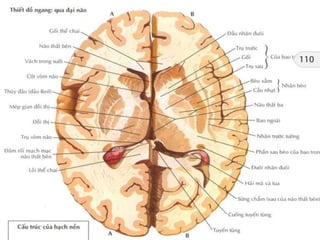

Giải phẫu cắt lớp sọ não

Axial !!!

Sừng trước

não thất bên

Thùy đảo

Não thất ba

Bể trên tiểu não

Đầu nhân đuôi

Đồi thị

Nhân bèo

Bao trong

Bèo sẫm

Cầu nhạt

Cánh tay trước

Thùy trán

Thùy thái dương

Tiểu não

Cầu não

Não thất tư

Bể trên yên

Khe Sylvius

Hành não

Sừng trước não thấtbên Thùy đảo Não thất ba Bể trên tiểu não